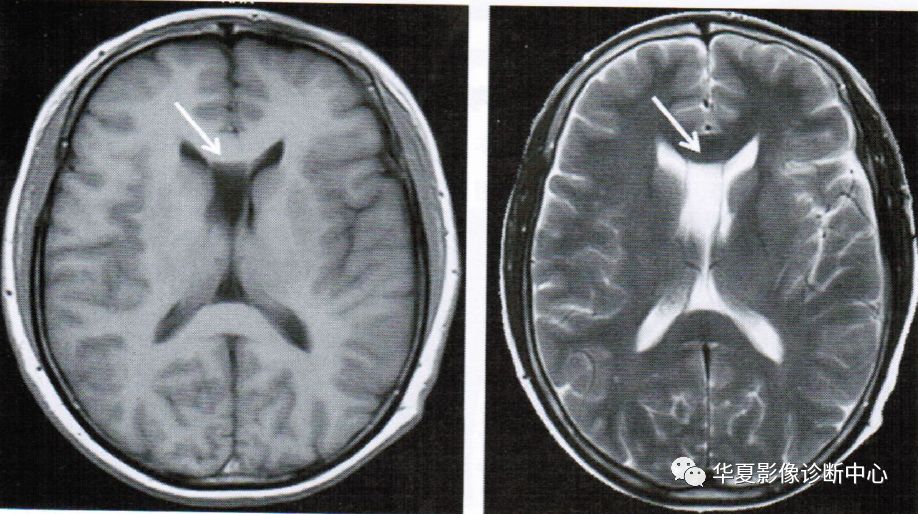

上图为透明隔囊肿

透明隔囊肿表现为透明隔两侧壁弯曲甚至膨隆,失去正常平行状态,且侧壁间距>10mm